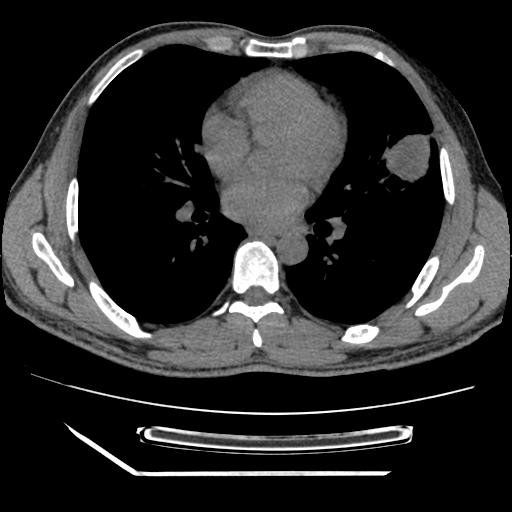

男,38岁,于2009年8月9日晚突发左侧胸痛,今x线提示左下肺阴影,为了明显确诊断,行ct检查,

血常规:嗜酸性细胞增高,单核细胞增高。

病灶发生在下叶,密度均匀,边缘模糊、毛糙,周围血管纹理增强扭曲改变,靠近胸膜处病灶胸膜反应明显。

支持考虑---球形肺炎。

左肺舌叶病变。主体病灶呈类圆形中心密度低,成液化趋势周边班片影分布

考虑肺脓肿

虽然实验室检查支持炎性病变,且病变内有坏死改变(中央呈大片状低密度影),但仍不能掉以轻心,鳞癌也可以有这种影像改变。